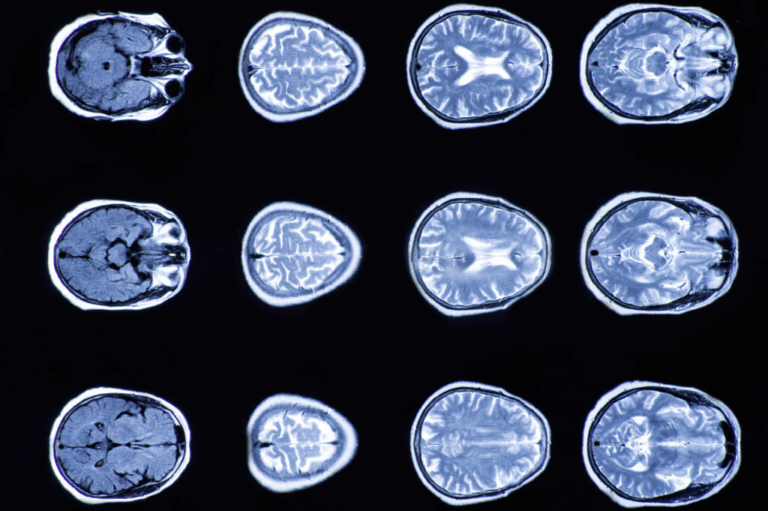

Signos y síntomas de una lesión cerebral traumática

Las lesiones cerebrales no siempre son visibles de inmediato. Algunos síntomas pueden tardar días o semanas en manifestarse. Los signos comunes de lesiones cerebrales traumáticas incluyen: